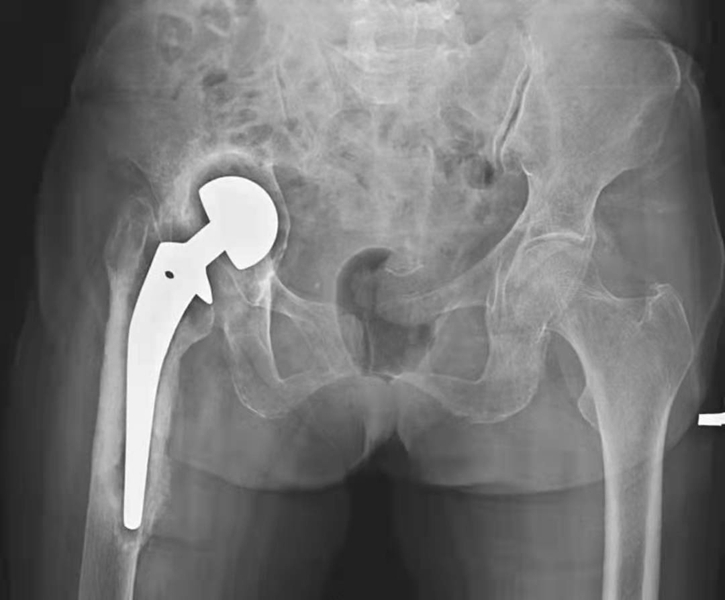

三、脱位

多发生在术后2~4周,发生率为0.3%~5.4%,通常为假头的前倾角过大以及关节屈曲性痉挛的原因造成。X线片是诊断脱位最佳办法,表现为人工髋关节正常位置关系失常,人工股骨头向外上方移位,位于髋臼假体外(图5)。

图5 左侧人工髋全脱位

平片,示左侧人工股骨头与髋臼关系失常,人工股骨头脱出髋臼向外上方移位